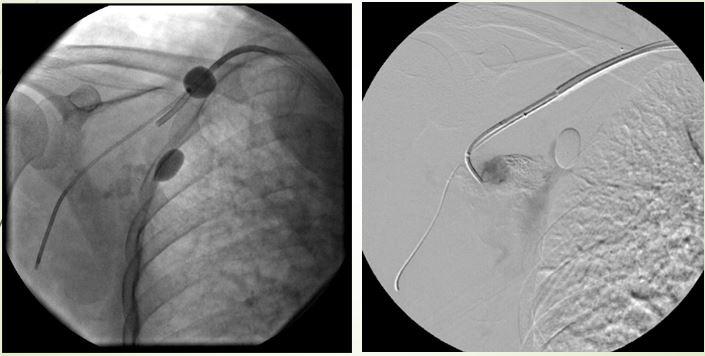

Cô gái trẻ ù tai trái từ nhỏ do rò động tĩnh mạch cảnh ngoài lưu lượng cao

Bệnh nhân nữ 22 tuổi vào viện có khối phồng đập vùng góc hàm trái, ù tai trái từ nhỏ, ngày càng lớn dần, chóng mặt tư thế… Bệnh nhân do một bác sĩ phẫu thuật mạch máu chuyển qua BS Trần Chí Cường, nhờ can thiệp nội mạch.

Rò động tĩnh mạch cảnh ngoài lưu lượng cao

Kỹ thuật dùng bóng kiểm soát dòng chảy và gây tắc

Bệnh nhân khỏi hoàn toàn sau can thiệp